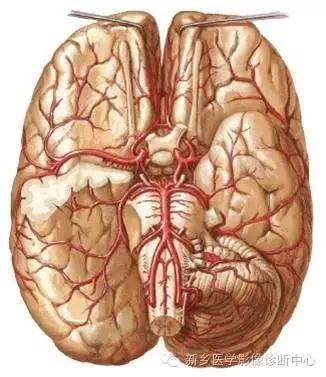

血管解剖基础

基底动脉尖位于以基底动脉顶端为中心的2cm范围内5条血管开口的部位。

5条血管即左右大脑后动脉,左右小脑上动脉和基底动脉顶端开口形成的一个“干”字型结构。

基底动脉是脑部后循环的轴心。它是由两侧椎动脉在脑桥和延髓交界处汇合而成,位于脑桥腹侧,贯穿其全程,并发出正中分支、旁正中分支、短旋支和长旋支。

后循环(posterior cerebral circulation),又称椎基底动脉系统,由椎动脉、基底动脉和大脑后动脉及其分支组成,主要供血给脑干、小脑、丘脑、海马、枕叶、部分颞叶及脊髓。

基底动脉的终末支为大脑后动脉(PCA),向中脑、丘脑、颞叶内侧和枕叶供血。

PCA分叉处的近端,基底动脉还发出小脑上动脉,向桥脑、中脑外侧部和小脑上面供血。

基底动脉顶端血管闭塞会出现其供血区域内的多发梗死,包括丘脑、中脑、小脑、枕叶、颞叶、脑桥上部和丘脑下部,往往呈双侧对称分布。

基底动脉向丘脑、中脑供血的深穿支,其动脉分支细,侧支循环差。故TOBS 以丘脑及中脑的缺血症状最为常见。